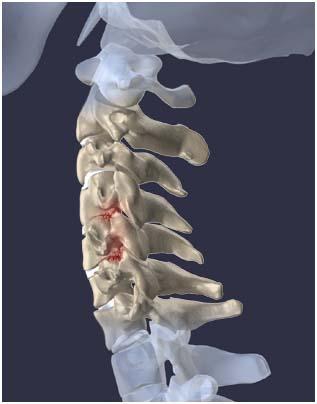

목을 받쳐주는 뼈를 경추라고 하는데 여기는 뼈가 7개 있고 이 뼈 마디마다 디스크라는것이 있습니다. 이 디스크의 역할은 척추 뼈 사이에 충격을 완화하고 운동할 수 있게합니다. 목디스크는 퇴행성 척추 질환으로 목 주위 근육, 인대가 장기간 압력을 받고 퇴행하여, 디스크가 자신의 역할을 하지 못하고 밀려나고 통증과 같은 목디스크 증상을 보이는 질병입니다. 이 디스크의 위치가 어디에 있는지에 따라 목 이외에도, 손이 저리거나 어깨가 아프고 두통과 같은 다른 목 디스크 증상을 일으킬 수 있습니다. 만약 여러분이 디스크를 그대로 방치하면, 몸이 마비되거나 호흡이 곤란한 상황에 처할 수 있기 때문에 여러분의 관심을 필요로 할 것입니다.

척수라는 중추신경이 목뼈를 통과하고 목 아래 감각과 운동신경에 영향을 미치기 때문에 목디스크 증상이 나타날 경우 신속한 대책이 필요합니다. 목디스크 치료는 일반적으로 초기 단계에서 대부분의 환자가 물리 치료 또는 약물을 통해 개선됩니다. 그렇지 않으면 신경 성형술과 차단술이라는 뼈 주사 목 디스크 치료법을 사용합니다.이 치료법은 통증이 나타나는 신경 부위에 약물을 주입하는 것입니다. 치료로 질병을 완전히 치료하는 것이 아니라 염증을 완화하고 통증을 줄이는 것이 중요합니다.

3개월 이상 비수술적 치료를 받았음에도 불구하고, 만약 그들이 호전되지 않는다면, 목디스크 치료 중 수술을 고려할 필요가 있습니다. 인조 디스크를 삽입하기 위해 절개를 통해 디스크를 제거하고 뼈를 하나로 묶는 것과 내시경 수술로 빠져나온 수핵 자체만 제거하는 방법이 있다고 합니다.